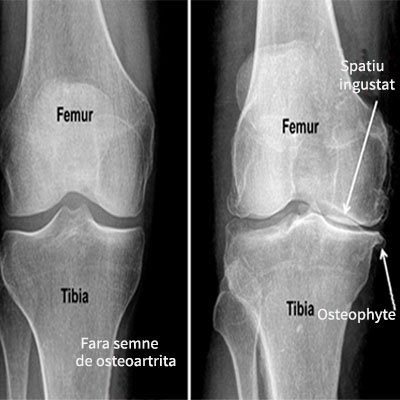

Cu ajutorul RMN, diagnosticul este precis, rapid si non-invaziv

Traumatismele genunchiului

Cele mai frecvente leziuni ale structurilor anatomice ale genunchiului